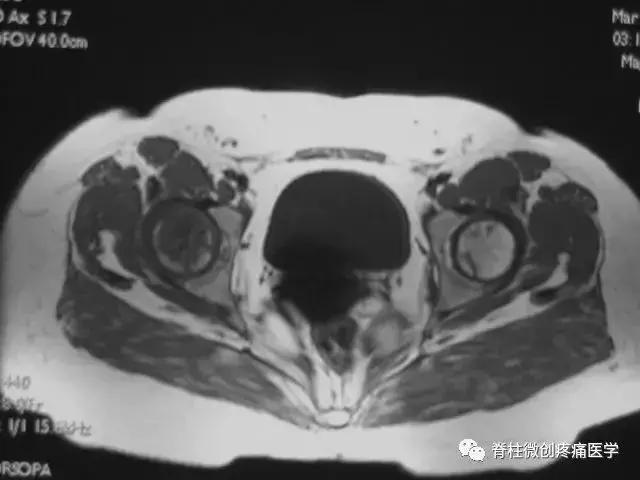

患者取仰卧位,扫描范围自髋臼上3cm至股骨粗隆下。

层厚5mm,层间距1mm连续扫描。

选择自旋回波SE序列T1WI、T2WI及STIR冠状面扫描,横轴位T1W扫描。